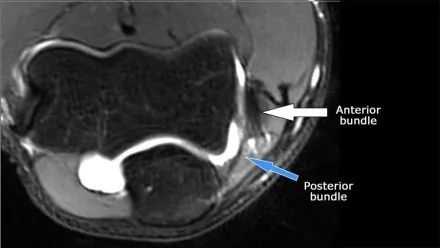

● 尺侧副韧带(UCL)位于内侧,它有三个组成部分。● 前束是最强的组成部分,是抵抗外翻力的主要限制因素。● 在MR上,这是最重要的结构。● 后束在鹰嘴上以扇形远端附着。它形成了肘管的后部。● 横向束从鹰嘴延伸到鹰嘴,所以它没有太多作用。

UCL(黄色)起源于共同屈肌腱原点正下方的内侧上髁下表面。它附着在冠状突内侧的一个小进程,称为高耸结节(sublime tubercle)。

在研究韧带时,尤其是UCL,始终使用轴向图像。如果你看内侧上髁,你会发现后束是一个薄的结构(蓝色箭头)。注意在肘管内的尺神经。

后束形成肘管隧道的地板。支持带覆盖肘管。请注意,前束更厚(白色箭头)。您可以看到前韧带和后韧带之间的区别,即使它们形成一条韧带。走向远端,我们会看到它们合并在一起以附着于崇高的结节。

下面的图我们看到UCL的两个连续冠状图像。在近端部分(箭头)看到一些高信号是正常的。注意它是如何牢固地附着在崇高的结节上并将其与下一个图像进行比较。